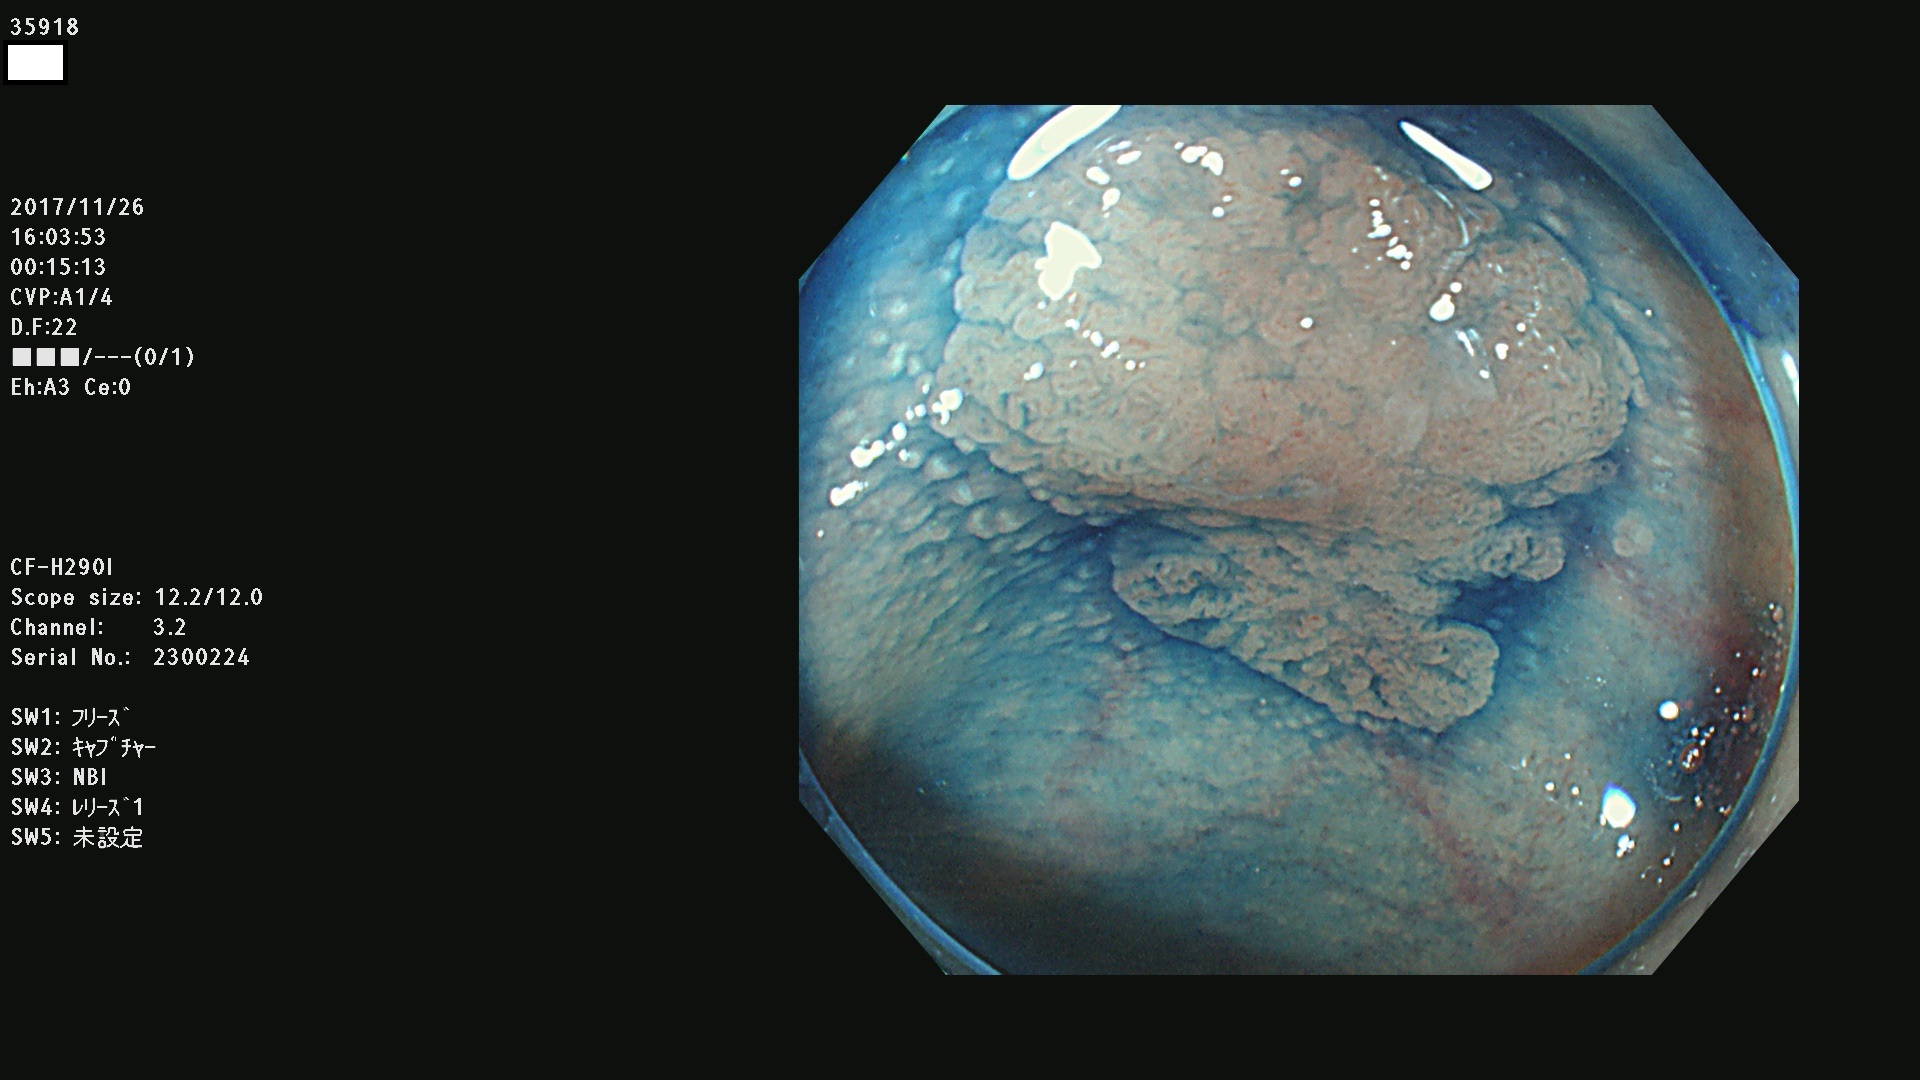

腺腫発見率43 % (カルテ番号 35900〜35999の100名の方の検査結果で集計)大腸癌検診最新情報

以下のカルテ番号の方に腺腫(Adenoma,Group3〜5)が見つかりました(集計法)

35900 35901 35904 35908 35912(SSA/Pのみ) 35914 35918 35922 35925 35926 35928 35931 35932 35933 35934 35937 35939 35943 35945 35947 35949 35951(SSA/Pのみ) 35952 35958 35959 35963 35964(SSA/Pのみ) 35965 35970 35972 35976(SSA/Pのみ) 35977 35978 35979(SSA/Pのみ) 35980(SSA/Pのみ) 35982 35983 35985 35991 35993 35995 35997 35999

発見困難で危険性の高い平坦型病変(上記100名より抽出) ![]()